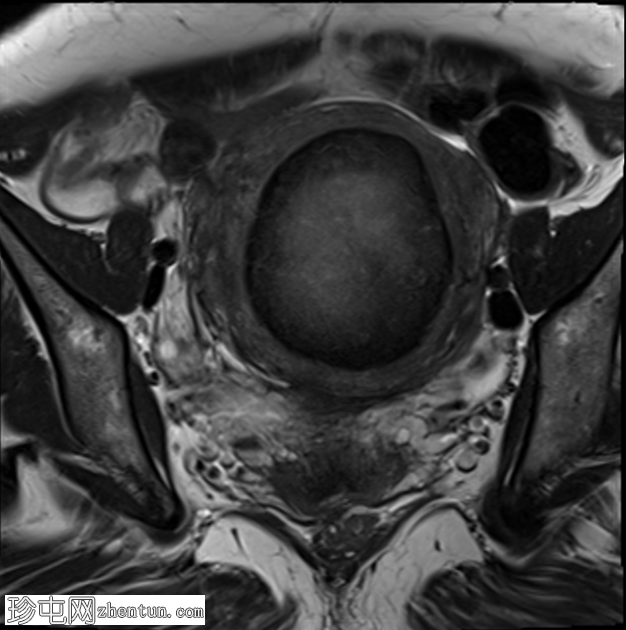

轴位

T2加权像

子宫前壁可见一边界清晰的壁内病灶,大小约7.8 × 7 × 6.8 cm。脂肪抑制T1加权像呈弥漫性高信号,T2加权像呈高信号伴低信号环,无扩散受限及对比增强。

此外,可见一个2厘米的带蒂浆膜下肌瘤,以及较小的肌壁内和浆膜下肌瘤;所有肌瘤均呈均匀强化。

盆腔内可见少量游离液体,可能为生理性。